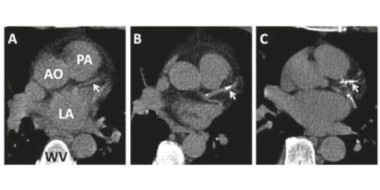

Elke huisarts voelt zich zekerder als een patiënt met pijn op de borst minder pijn voelt na het bekende tabletje onder de tong. Een cardiale oorzaak van de pijn wordt in dat geval veel waarschijnlijker. Het klopt ook mooi met onze pathofysiologische inzichten: het vat is vernauwd en de…